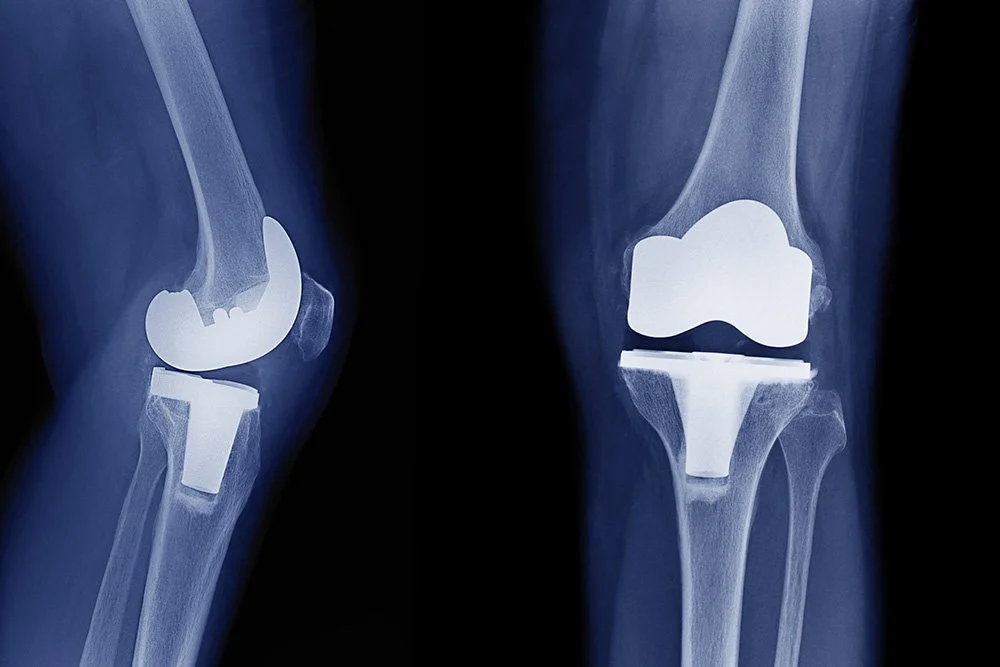

What Knee Replacement Material Lasts the Longest?

Modern implants use several types of knee replacement materials, including traditional metal-on-polyethylene (cobalt-chromium and plastic), metal-on-metal, and ceramic options. Today’s designs focus on reducing friction, resisting corrosion, and mimicking natural motion to improve comfort and longevity.

What’s the Difference Between a Partial and Total Knee Replacement?

Dr. Nathan Cafferky, a distinguished orthopedic surgeon and joint replacement specialist at The Steadman Clinic in Vail, Colorado, is dedicated to helping patients understand their options for knee replacement surgery. In this article, Dr. Cafferky delves into the key differences between partial knee replacement and full knee replacement, guiding patients toward informed decisions about their care.